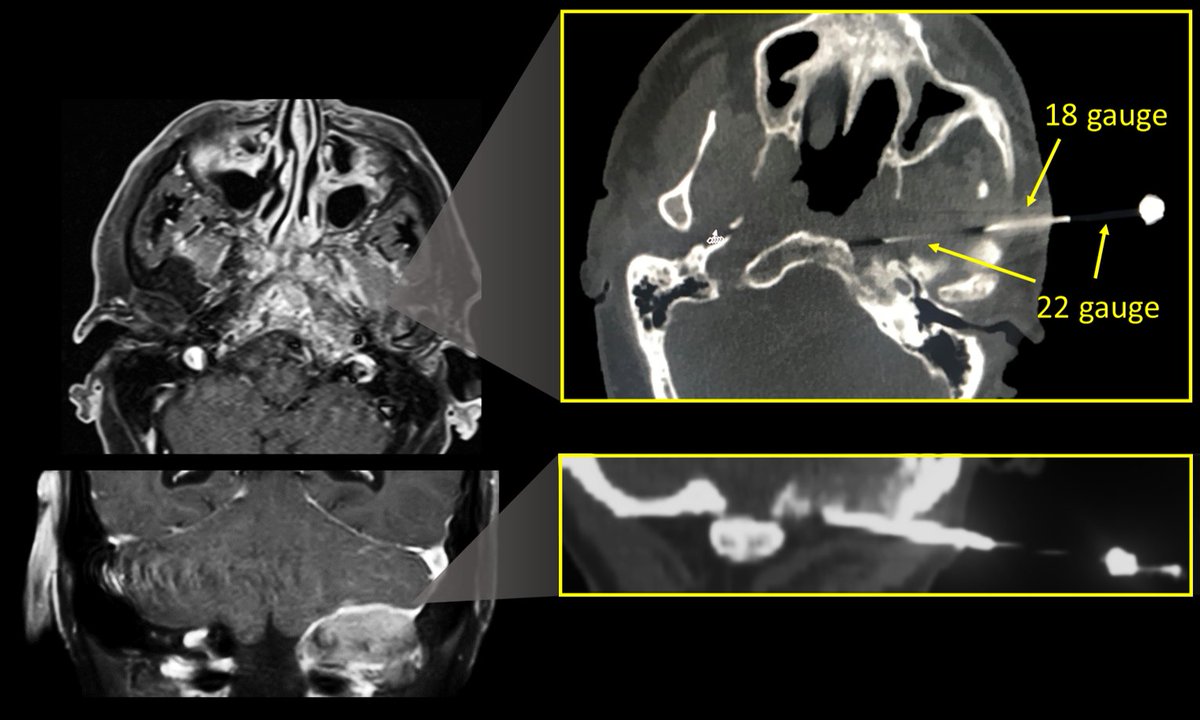

"You might feel a little sting." Don't be afraid to biopsy the skullbase! Examples of skullbase biopsies with a biopsy system I jerry-rigged together using an 18g medication draw needle as an introducer and a 22g spinal needle to biopsy. #radiology #neurosurgery #NeuroRad